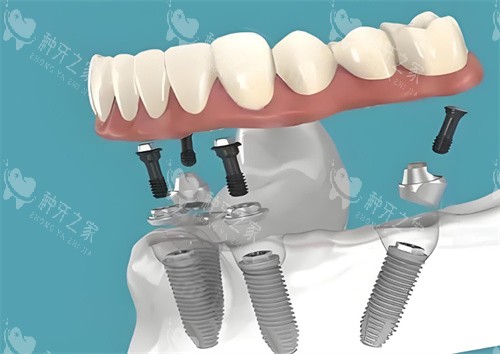

做半口或全口种植牙6年后,使用者普遍收获了咀嚼功能重塑、口腔状态稳定、生活质量提升的正向体验。不同修复技术、不同年龄段的网友,均反...